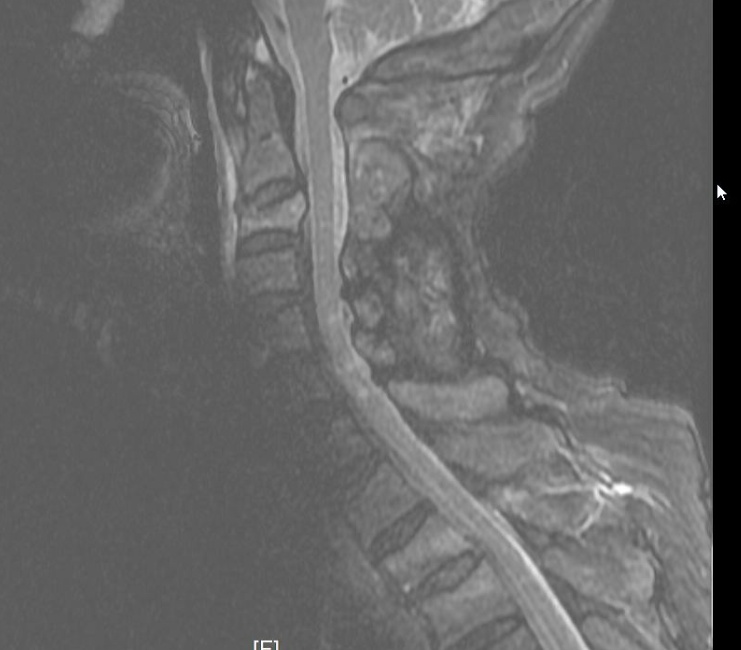

▲颈部带金属的膏药贴导致的伪影